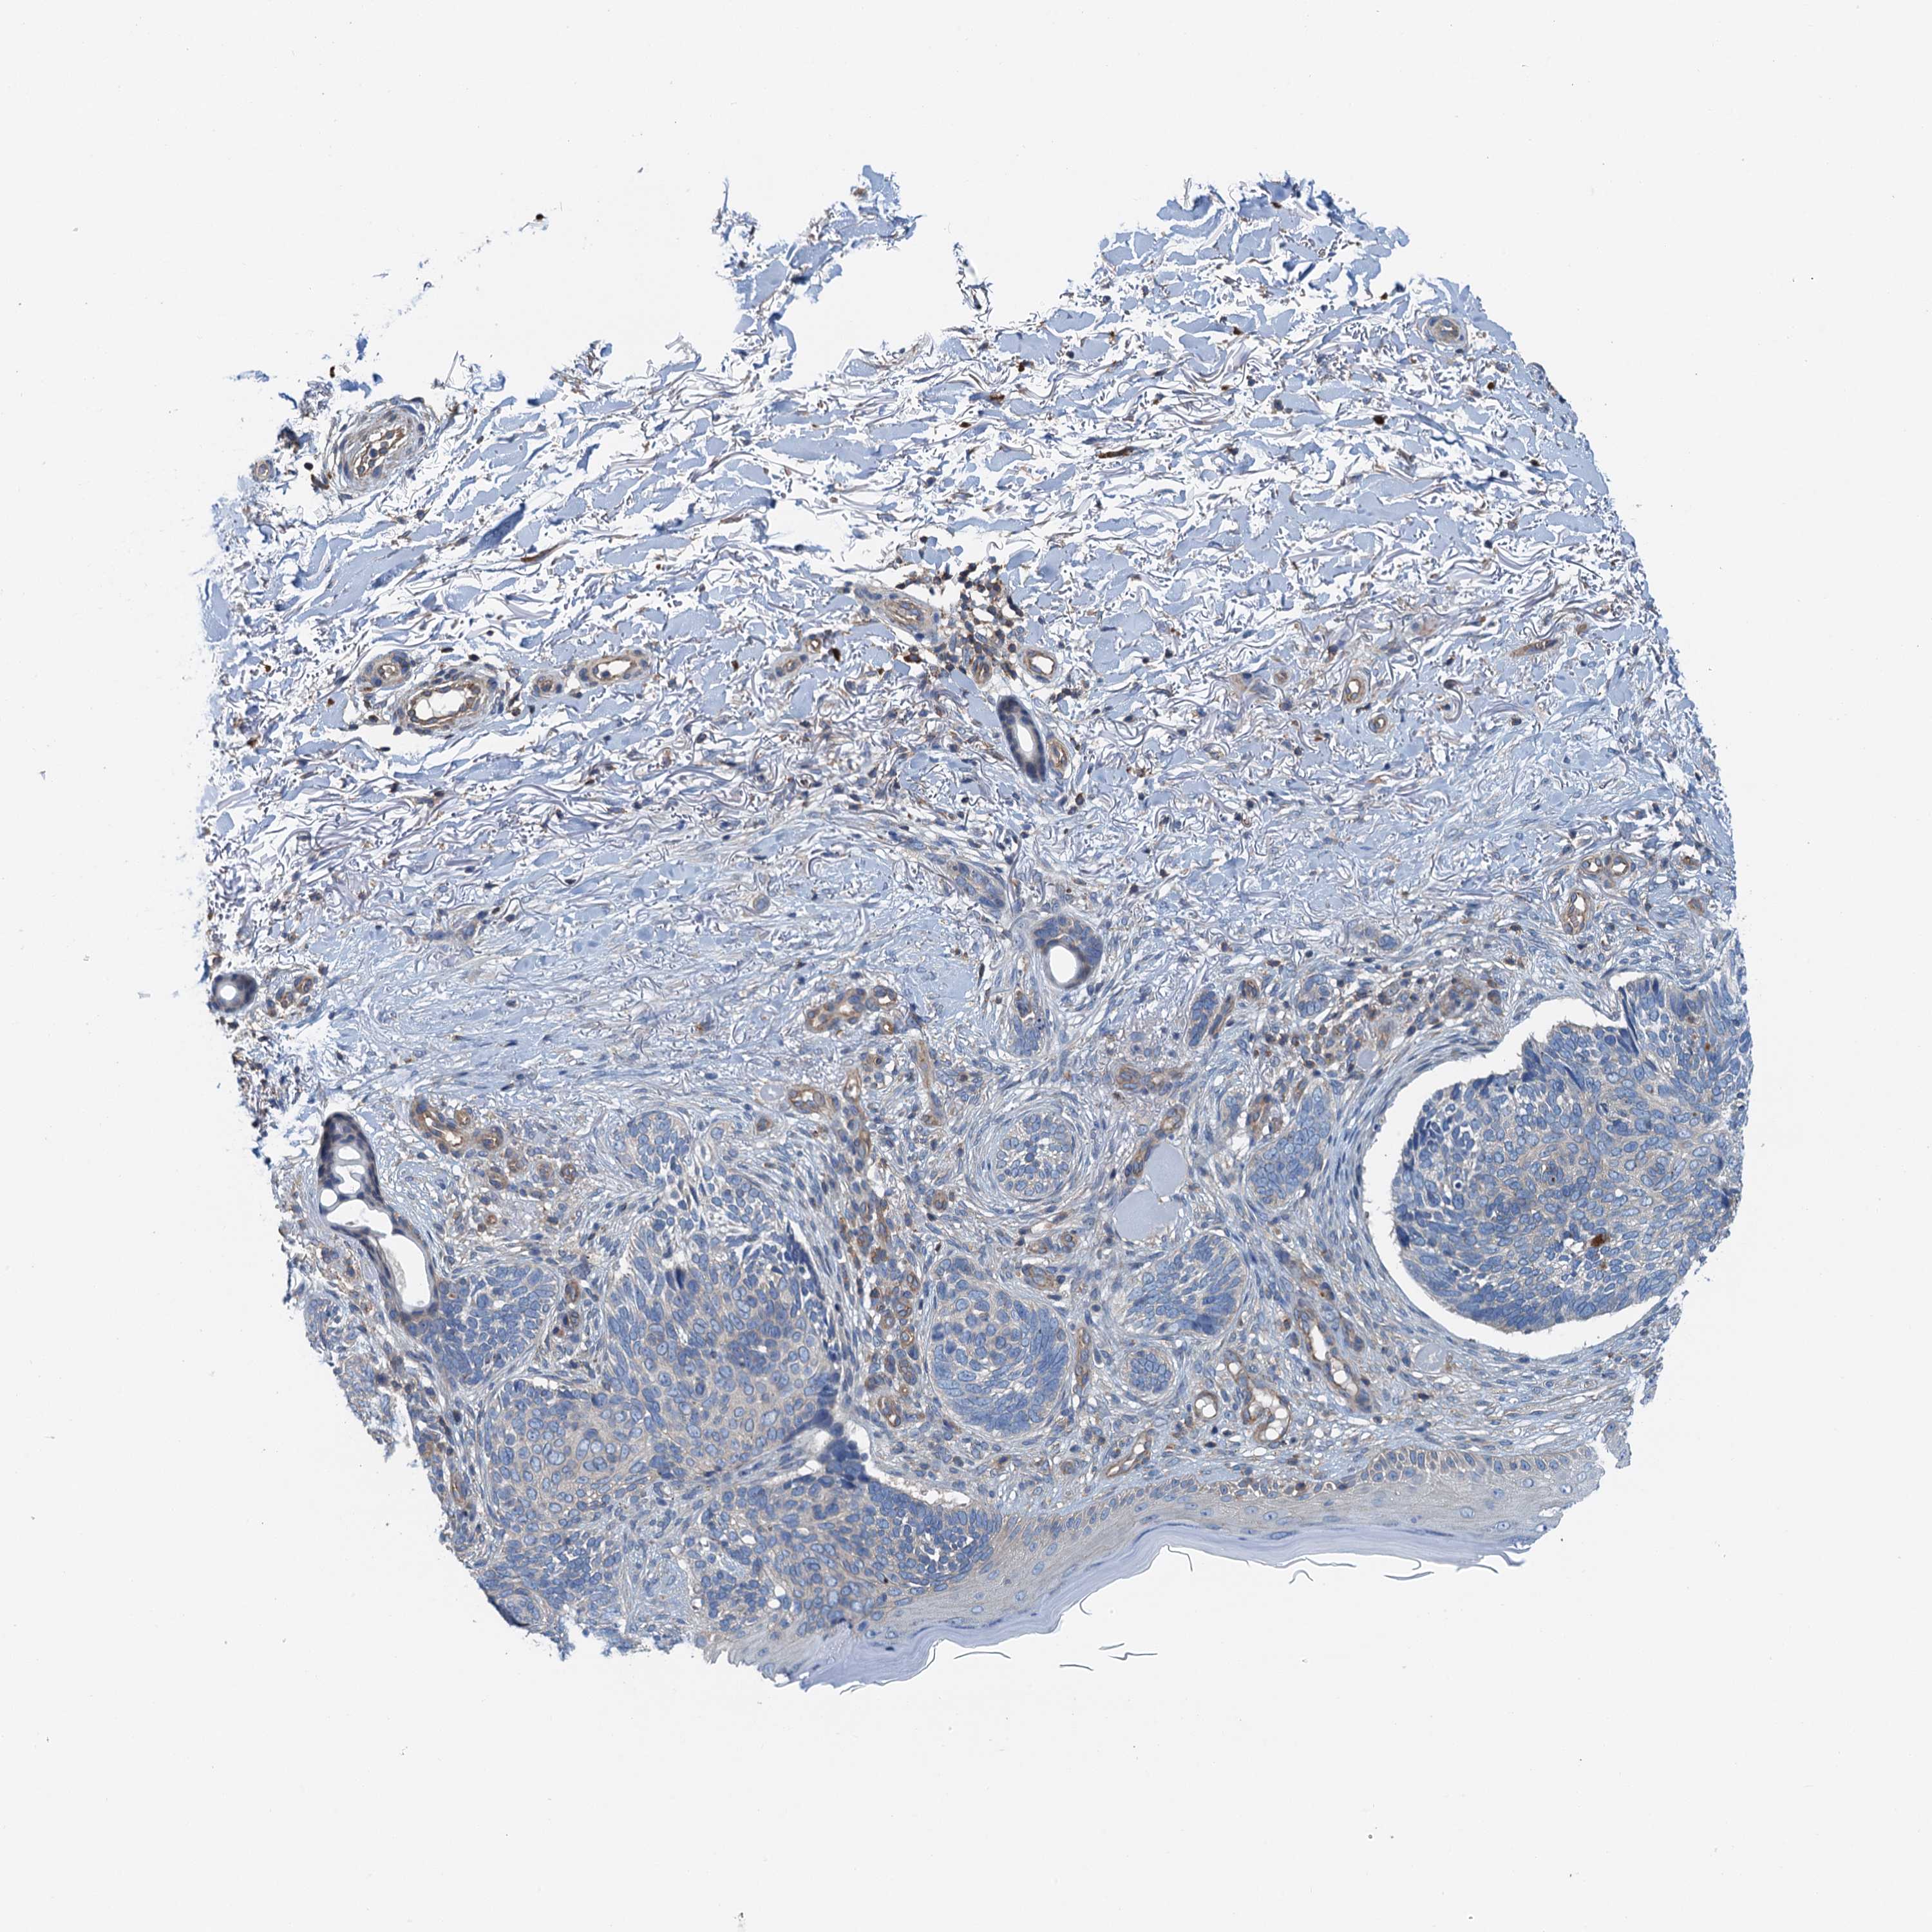

Basal cell and squamous cell cancer

SKIN CANCER - Protein expressioni

A mouse-over function shows sample information and annotation data. Click on an image to view it in a full screen mode. Samples can be filtered based on level of antibody staining by selecting one or several of the following categories: high, medium, low and not detected. The assay and annotation is described here.

Each image is clickable and will lead to virtual microscopy that enables deeper exploration of all samples and also displays staining intensity scores, fraction scores and subcellular localization as well as patient and tissue information for each sample.

Antibody HPA041000

Staining

High

Medium

Low

Not detected

Intensity

Strong

Moderate

Weak

Negative

Quantity

>75%

75%-25%

<25%

None

Location

Nuclear

Cytoplasmic/membranous

Cytoplasmic/membranous,nuclear

Basal cell carcinoma